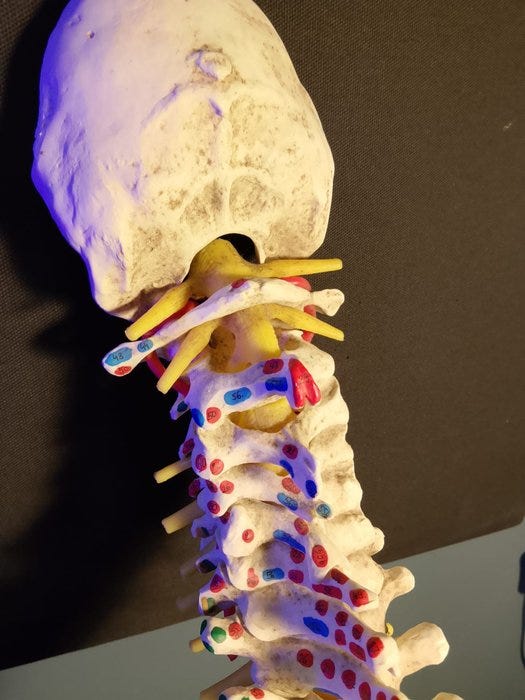

Denne 1:1-naturlige størrelse hvirvelsøjlemodel på 83 cm viser i detaljer alle hovedtræk ved hver hvirvelsøjle, herunder rygraden, nervetråde (nerverødder), vertebrale arterier, intervertebrale skiver, tværgående processer og snit af rygsøjlen. Forskning og studier

Modellen er særligt egnet til visning af en række patologiske misdannelser (rygsøjlens scoliose, lordose, kyfose). Der vises også føle- og spinalender. Den står på en basiskonstruktion. Så kan du levende forklare relevante kundskaber for eleverne gennem modellen, få eleverne til at forstå og hurtigt mestre